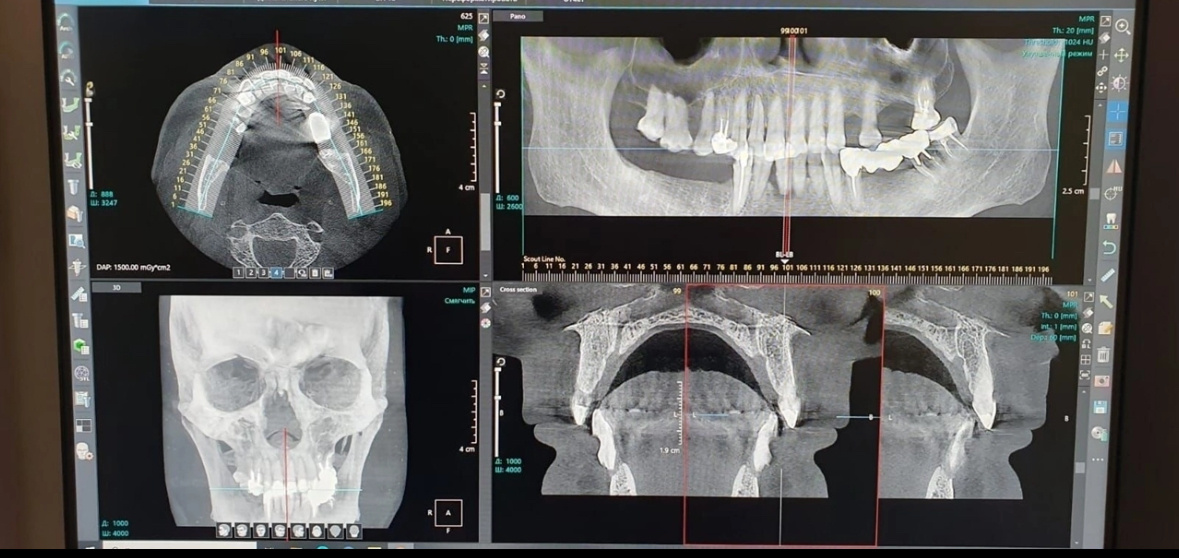

Компьютерная томография (КТ) – незаменима для диагностики в стоматологии.

Бывают ситуации, когда имеющиеся воспалительные процессы, опухолевые образования и кисты еще не вызывают тревожных симптомов у пациента, но стоматолог уже видит их на полученном трехмерном изображении.

Во время исследования компьютерный томограф послойно сканирует мягкие и твёрдые ткани с высокой точностью, после чего обрабатывает изображения и создаёт трёхмерную модель исследуемого участка.

В клинике «Академия VIP» в Нижнем Новгороде мультивекторная диагностика выполняется на аппарате Point 3D — он обеспечивает быстрое сканирование и позволяет одновременно получать изображения для 3D-модели и панорамного снимка зубов всего за одно обследование. Это не просто КТ — это новый стандарт точности.

Мультивекторное сканирование на Point 3D Combi 500C — ключевой этап подготовки к имплантации. В отличие от обычной КТ, оно учитывает разные углы и глубину, что особенно важно в сложных клинических случаях и позволяет установить имплант с максимальной точностью.